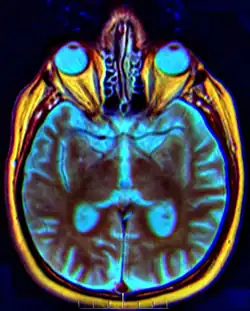

Chiasma opticum (Χ) im MRT-Bild